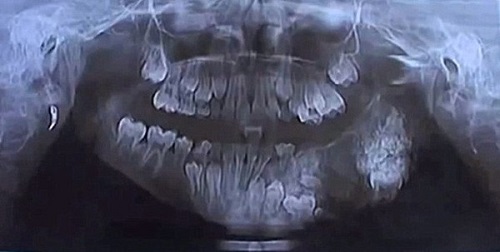

Được chuẩn đoán mặc căn bệnh u răng – một dạng u lạ gây ảnh hướng tới xương hàm và lợi, cậu bé 7 tuổi đã phải trải qua một cuộc phẫu thuật để nhổ bỏ 80 chiếc răng thừa.

Mặc dù mới chỉ bước sáng tuổi thứ 7 nhưng một cậu bé sống tại thành phố Mumbai, Ấn Độ đã có một hàm răng "khủng" với số lượng lên tới hơn 100 cái, ước tính nhiều gấp gần 3 lần so với người thường. Cuối cùng, sau ca phẫu thuật kéo dài 4 tiếng đồng hồ, các bác sĩ đã nhổ bỏ thành công 80 chiếc răng thừa ra khỏi miệng cậu bé.

Được biết, cậu bé không tiết lộ danh tính này đã được gia đình đưa tới Bệnh viện Maharaja Yashwantrao ở thành phố Mumbai sau khi miệng bị sưng to trong khoảng thời gian kéo dài. Qua kiểm tra sơ bộ, các bác sĩ đã phát hiện gần trăm khối u có hình dáng và cấu tạo giống răng đang thi nhau mọc lên từ hàm trên của cậu bé.

Theo các bác sĩ nha khoa của Bệnh viện Maharaja Yashwantrao, những chiếc răng thừa này tập hợp lại với nhau, tạo thành áp-xe trong miệng cậu bé. Các kết quả xét nghiệm, chụp chiếu khác cho thấy, cậu bé đã mắc căn bệnh u răng, một dạng u lạ gây ảnh hướng tới xương hàm và lợi. Và trường hợp mắc bệnh sớm như cậu bé này được đánh giá là hiếm gặp.

Hình chụp X-quang xương răng của cậu bé.

Những bệnh nhân bị u răng thường mọc các khối u có hình dáng và cấu tạo giống răng. Do được hình thành từ men và ngà răng nên người ta vẫn thường coi nó là răng thừa.

Sau khi xử lý áp-xe, các bác sĩ đã tiến hành nhổ bỏ toàn bộ số răng thừa ra khỏi hàm trên của cậu bé.